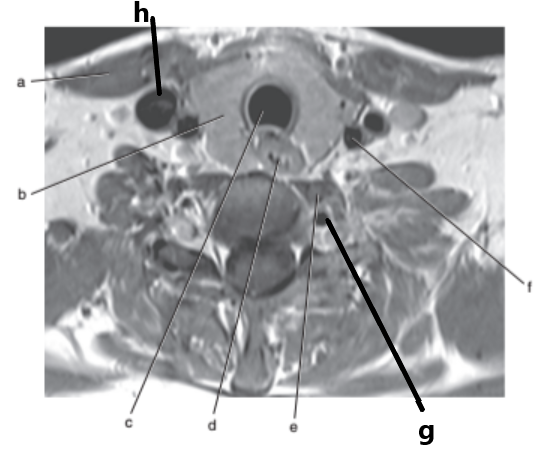

What imaging plane is this ?

transverse

What is letter a ?

Internal jugular vein

What is letter f ?

Spinal cord

What is letter h ?